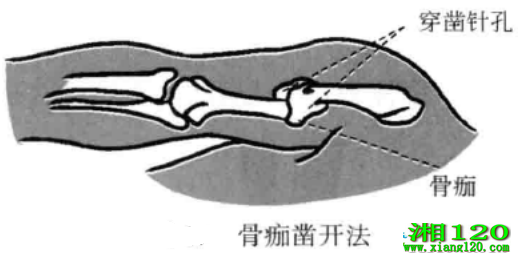

7、骨痂凿开法

当骨干骨折畸形愈合影响正常功能时,可用小针刀穿凿数孔,将其手法折断再行复位。如是较小骨师,将小针刀刀口线沿患骨纵轴垂直刺入骨痴,在骨折间隙或两骨间隙穿凿二三针即可分离。如是较大骨痴时,用前法穿凿七八针后再行手法折断,此时手法折断不会再将好骨折断,只会在骨捅需要折断的位置折断。